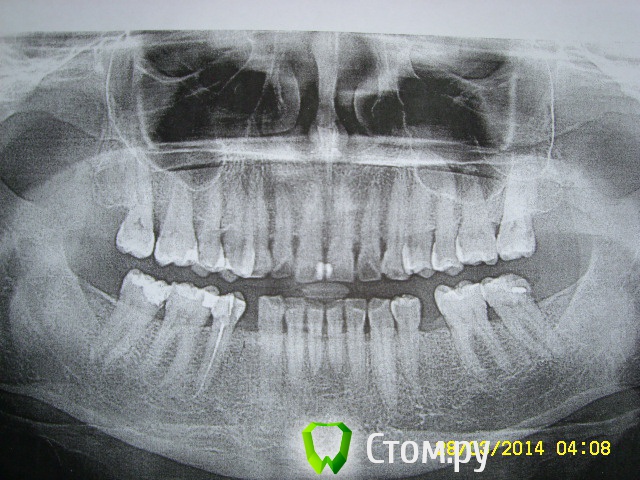

elena1971 Опубликовано 22 апреля, 2015 Автор Поделиться Опубликовано 22 апреля, 2015 После 7 месяцев болезненных ощущений сходила на консультацию к другому ортодонту. Врач сказал, что некоторые брекеты спозиционированны неверно. Уважаемые ортодонты, посмотрите пожалуйста фото до и после 5.5 мес. лечения. Интересно Ваше мнение. Ссылка на комментарий

elena1971 Опубликовано 23 апреля, 2015 Автор Поделиться Опубликовано 23 апреля, 2015 Вам клиника предоставляет такие фото после каждого посещения? места под импланты внизу, кажется по фото , что недостаточно, Ваш ортопед должен смотреть. Нет, не после каждого посещения. Одно фото до установки брекетов, второе - через почти 6 месяцев лечения. До имплантов еще очень далеко. Вообще, я думаю о смене врача. 7 месяцев лечения - длительные болезненные ощущения, передние верхние зубы ушли вперед. Справа верхние зубы ударяются о нижние, непонятно что с центром. Все процедуры проводит гигиенист, врач только бегло смотрит. Гигиенист в процессе лечения делает ошибки (в последний раз гнутую дугу поставила неправильно, сместив значительно центр и изгиб дуги попал в замок). После пары дней сильной боли врач поставила дугу по центру. Но это только мое мнение, хотелось бы узнать мнение профессионала. Ссылка на комментарий

Yana guapa Опубликовано 23 апреля, 2015 Поделиться Опубликовано 23 апреля, 2015 Нет, не после каждого посещения. Одно фото до установки брекетов, второе - через почти 6 месяцев лечения. До имплантов еще очень далеко. Вообще, я думаю о смене врача. 7 месяцев лечения - длительные болезненные ощущения, передние верхние зубы ушли вперед. Справа верхние зубы ударяются о нижние, непонятно что с центром. Все процедуры проводит гигиенист, врач только бегло смотрит. Гигиенист в процессе лечения делает ошибки (в последний раз гнутую дугу поставила неправильно, сместив значительно центр и изгиб дуги попал в замок). После пары дней сильной боли врач поставила дугу по центру. Но это только мое мнение, хотелось бы узнать мнение профессионала. судя по первоначальным фото у Вас и до лечения "верхние зубы ударялись о нижние", кардинальной разницы в прикусе не видно. Какая основная цель ортодонтического лечения у Вас? создать место? если будут стоять просто раскрывающие пружины, то передние зубы и будут уходить вперед. чтобы этого не происходило, то нужно делать акцент на боковых участках, и именно боковые зубы смещать назад в большей степени, а передние вперед в меньшей степени. для этого хотя бы минивинты как дополнительная опора должны быть установлены, и применена многопетлевая техника. У Вас, судя по фото, ни того ни другого. Ссылка на комментарий